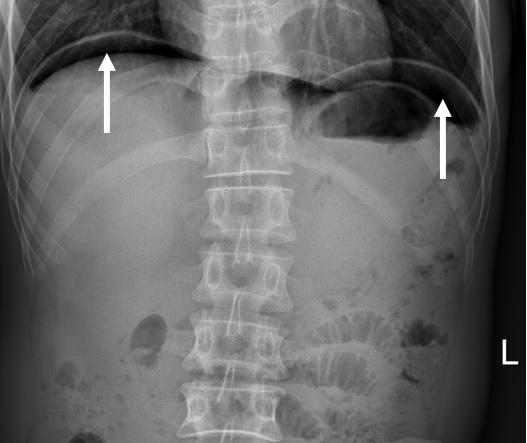

胃肠道是空腔管状消化器官,上、下端与外界相通,中间容纳着食物、粪便等不同性质的固体、液体及气体成分。当胃肠道因溃疡、炎症或其它原因而发生穿孔时,管腔内的这些内容物就会“跑”到胃肠道外的腹膜腔,液体、固体向下流注到盆腔不好观察,但轻的气体则会向上积聚到腹腔最上部,即膈肌下方。

所以,怀疑胃肠道穿孔时,主要的关注点在于能否发现管腔外的气体积聚。换句话说,如果在胃肠道的腔外发现有气体影像,最近又没有做过手术,那基本上就可以肯定胃肠道已经有穿孔了。

不过,如果患者的溃疡病史明确,这次的腹痛症状特点又符合穿孔,是不是必须先做CT,那就可以打个疑问号!因为气体影像在普通X线检查时也容易被观察到,照个腹部平片不是比CT检查更方便快捷而且便宜吗?

事实上,目前在怀疑胃肠道穿孔时,完全可以将X线检查作为首选,有时甚至也可用腹部透视,更加简单便捷,只是透视不太好留下客观记录,影像显示不太清晰,是其固有的缺点。

必须指出:想要诊断和鉴别胃肠道穿孔,无论是X线透视,还是摄片,一定要让患者站起来,实在站不了,也要坐着。我有两句相对诙谐的说法:“怀疑胃肠穿了孔,站着照片别怕疼!”因为只有这样,腹部最高的位置才是膈下,才会容易看到积聚的气体影,否则看不清,做了也白做!

立位X线平片显示膈下气体影,强烈提示胃肠道穿孔